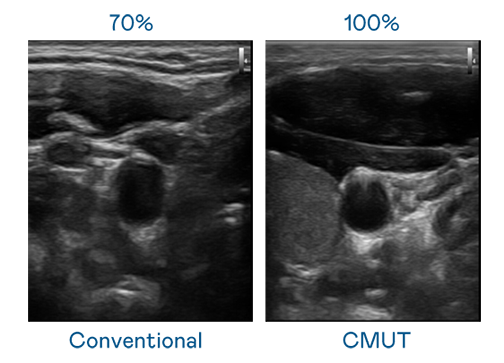

CMUT 技术是一种用电容式微机电元件来产生超音波讯号的技术。与传统 PZT 压电式技术相比,CMUT 频宽增加 30%,更宽频的超音波讯号让影像解析度大幅提升,是实现高影像品质医疗超音波扫描、促进精准医疗发展的关键技术。

大频宽带来超清晰影像

超音波影像的解析度高低,首先取决于探头能发出的讯号频宽。AG百家乐 CMUT 可提供高清晰的超音波讯号,提供高频宽、高灵敏度、影像纹理细节更高的超音波影像,协助医护人员缩短影像判读时间及利用精准的医疗影像进行诊断。